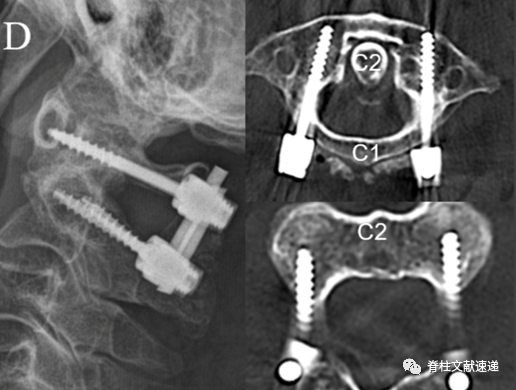

C2螺钉除了pars螺钉和椎弓根螺钉技术,还有介于两者之间的改良技术。如下图所示,这种改良螺钉进针点较标准椎弓根螺钉偏内、偏尾端,螺钉轨迹沿峡部皮质走行,内倾角度较椎弓根螺钉小的多(0-15度),类似Magerl螺钉。头端骨质保留较多。螺钉前端止于C2侧块关节面,亦可突破关节面,不像椎弓根螺钉止于C2椎体腹侧皮质,因而椎体前方结构损伤可能性很小。螺钉长度22-28mm。强度较标准椎弓根螺钉固定强度略差,较Pars螺钉高得多。下图所示为这种改良技术示意图和透视图。